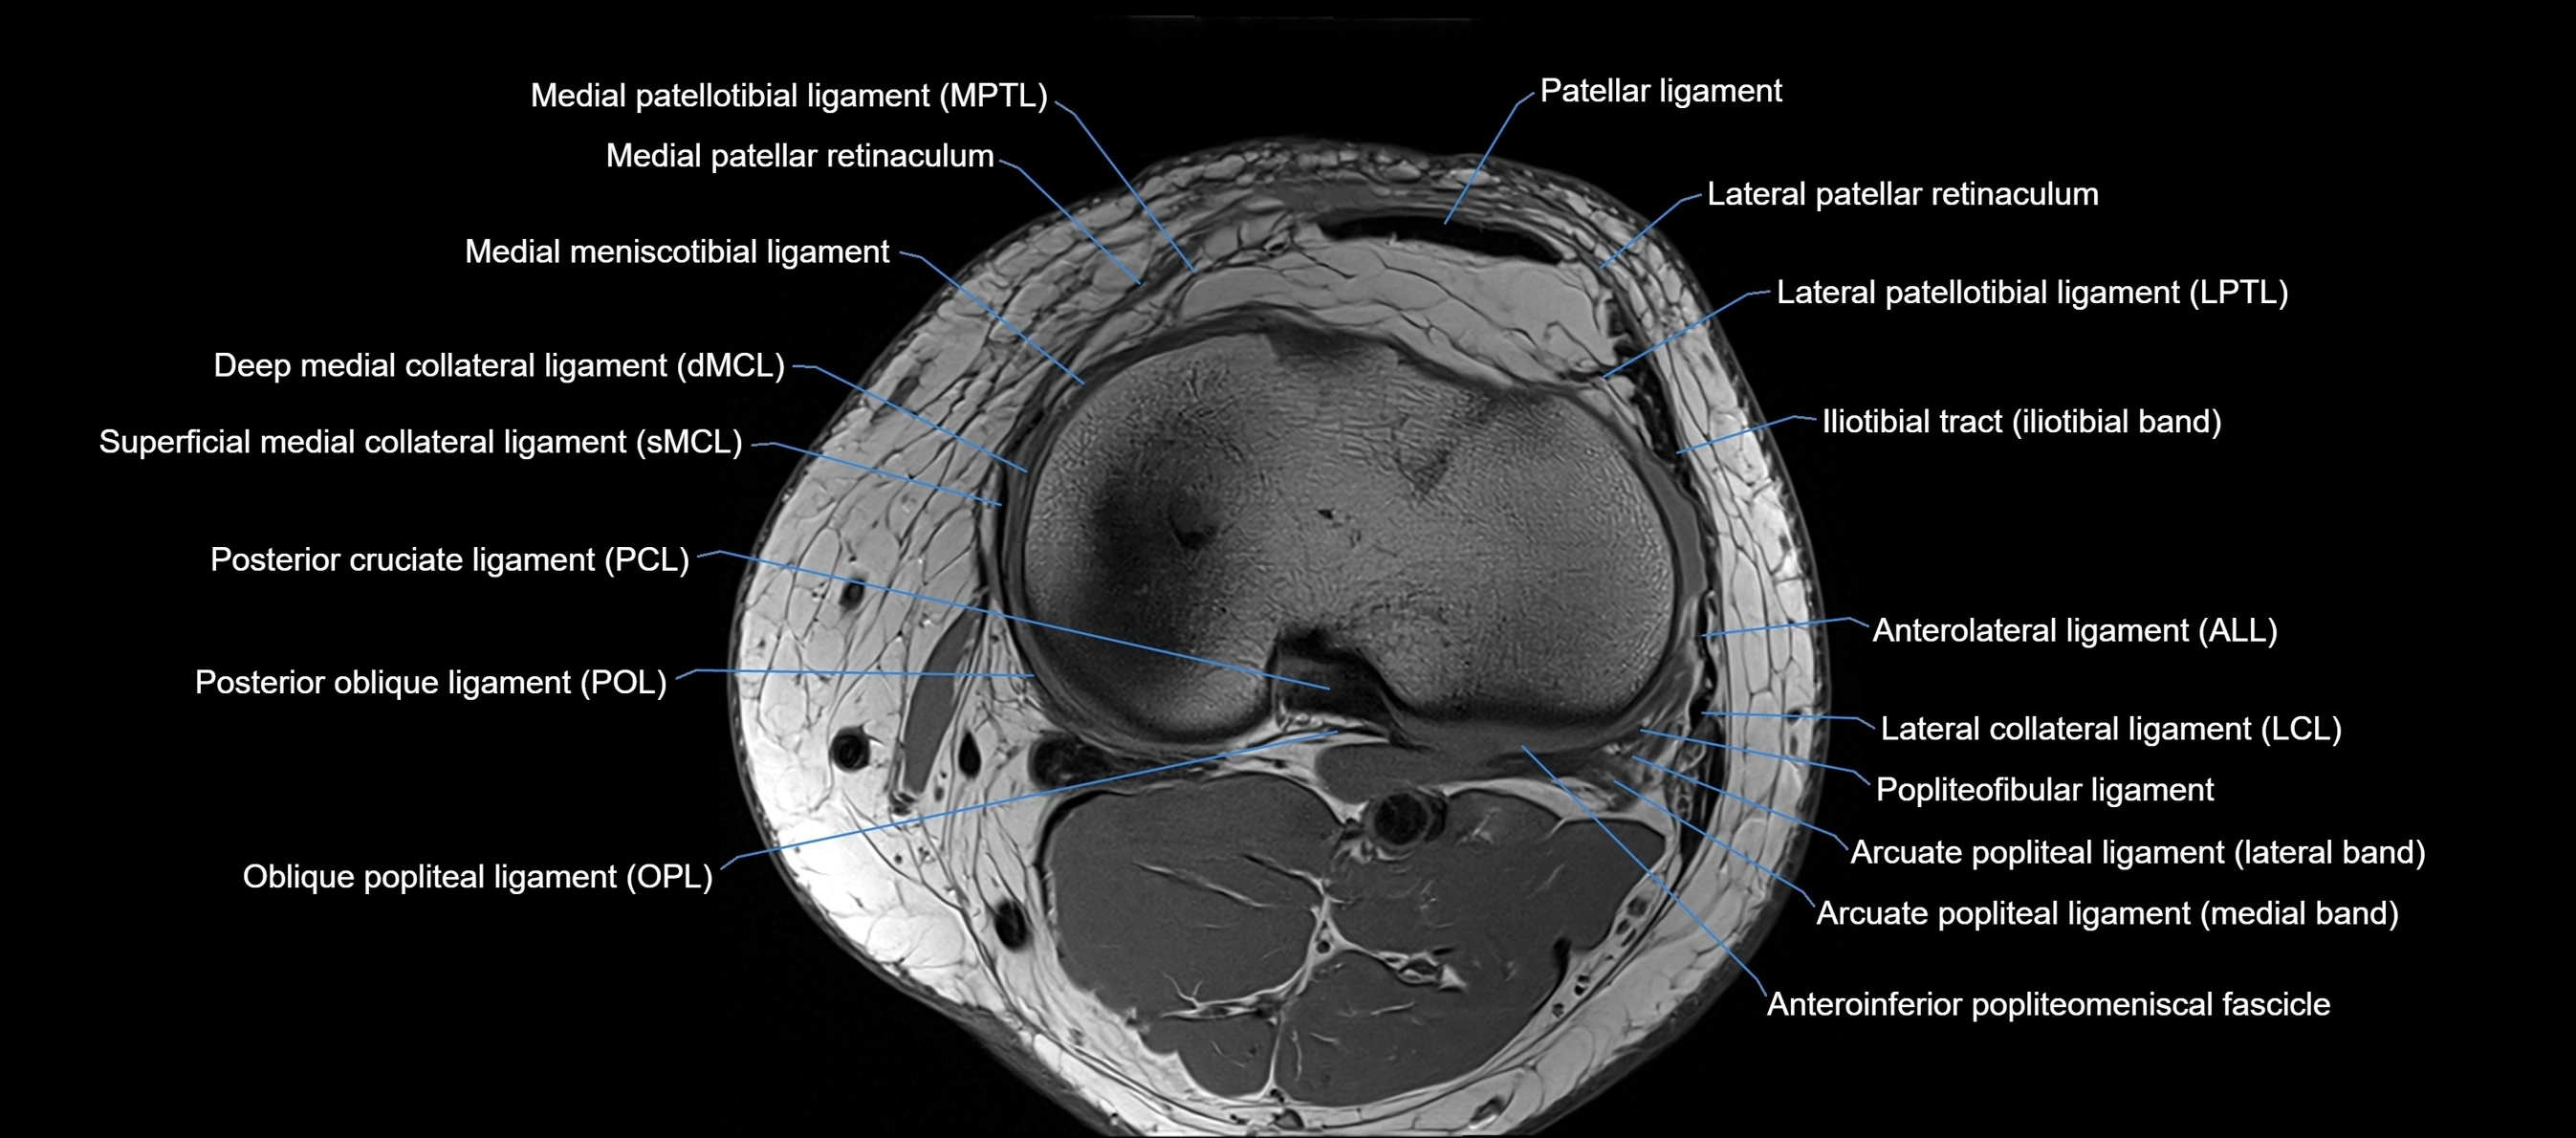

MRI images

image